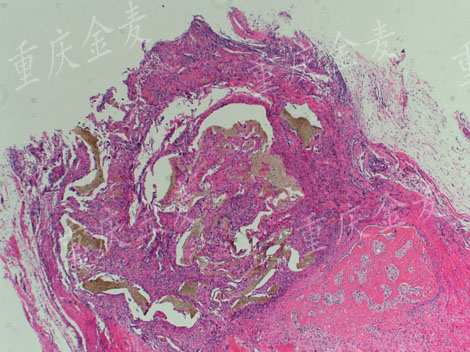

股骨髁外侧缺损4周后H&E染色

股骨髁外侧缺损材料修复4周后H&E染色